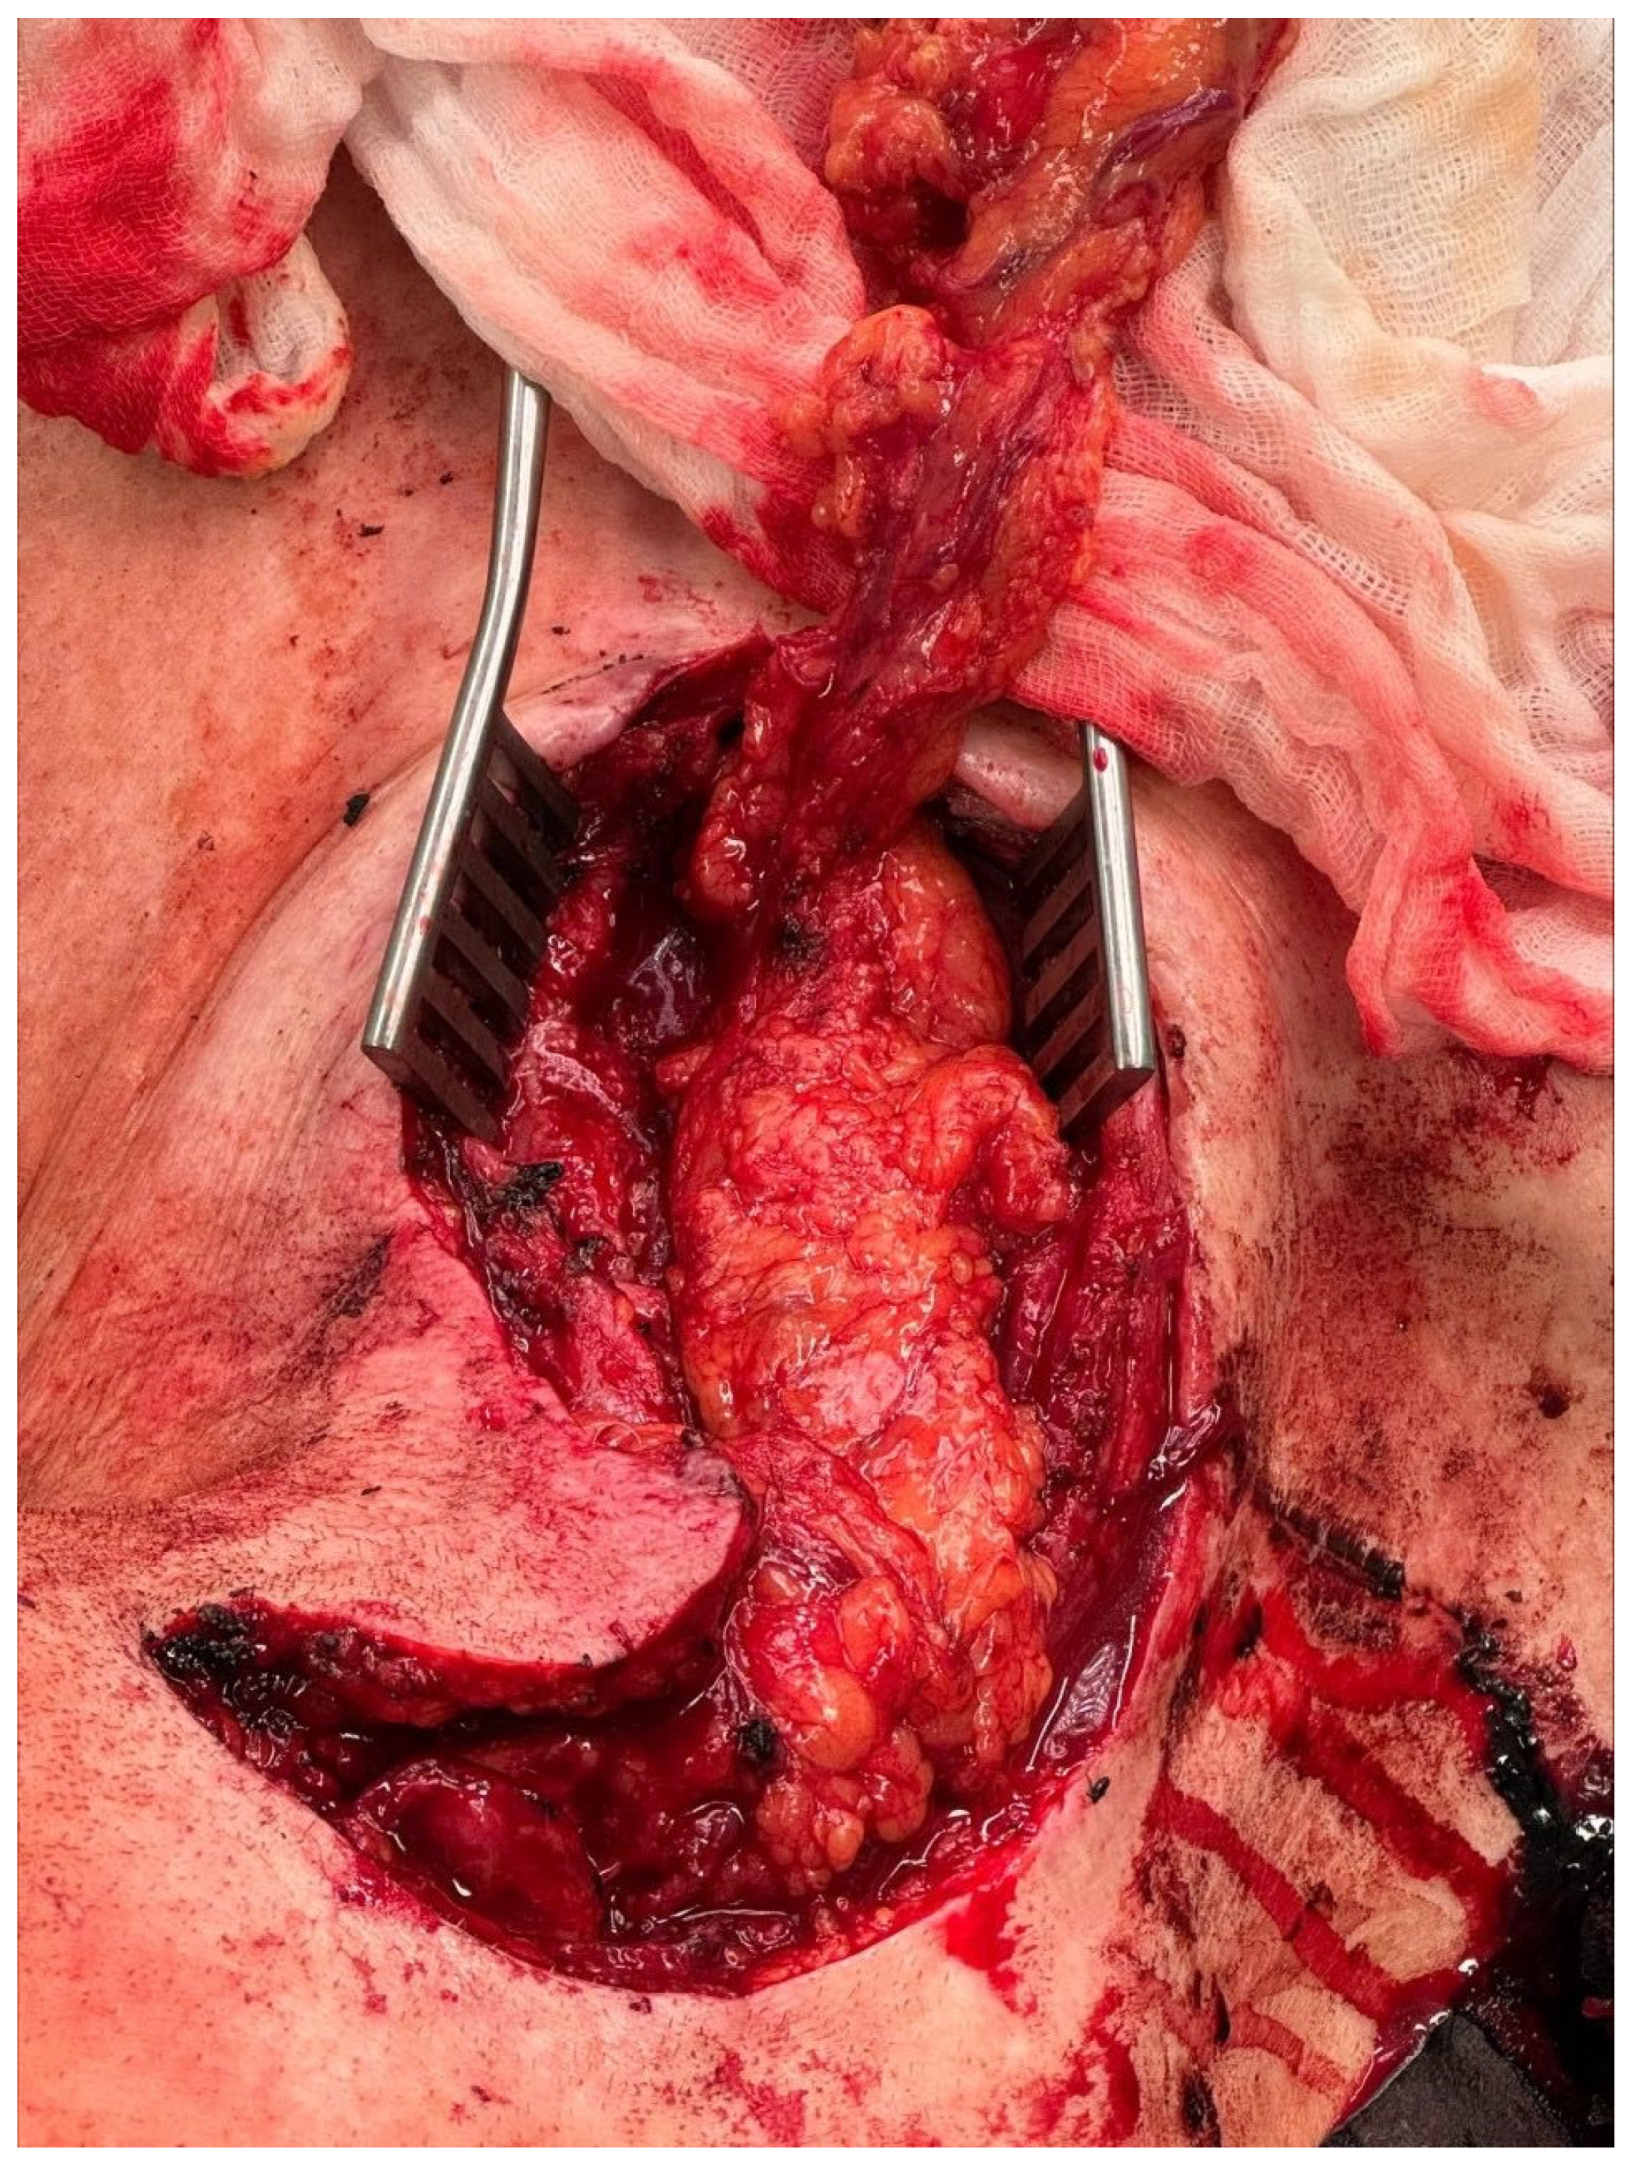

2. Case Report